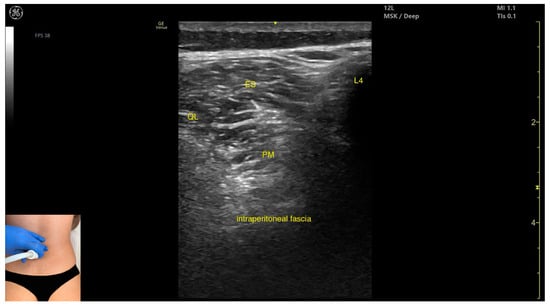

3.3.3. Key Ultrasound Landmarks

- Muscle position: It is the deepest muscle mass at this level.

- External fascia: It presents a pronounced fascia that separates it from the erector spinae and quadratus lumborum, aiding in safe botulinum toxin injection.

- Dynamic evaluation: During dynamic evaluation, when scanning proximo-medially toward the costal arch, its origin is visualized from the T12 to L5 vertebrae.

- Contraction is visible during hip flexion, as well as lumbar spine flexion and lateral inflection maneuvers.

- The psoas major can also be visualized using a longitudinal transducer position, placed superior to the iliac crest and 2 cm lateral to the L4 spinous process. In this view, both the psoas major and the overlying quadratus lumborum are seen superficial to the intraperitoneal space.

| Psoas Major | 2 cm lateral to L4 spinous process; 1 cm proximal to the iliac crest | Erector spinae muscles; quadratus lumborum (superficial); intraperitoneal space (deep to the muscle) | Transverse or longitudinal scan on posterior trunk | Avoid intraperitoneal space; inject only when muscle is clearly visualized |